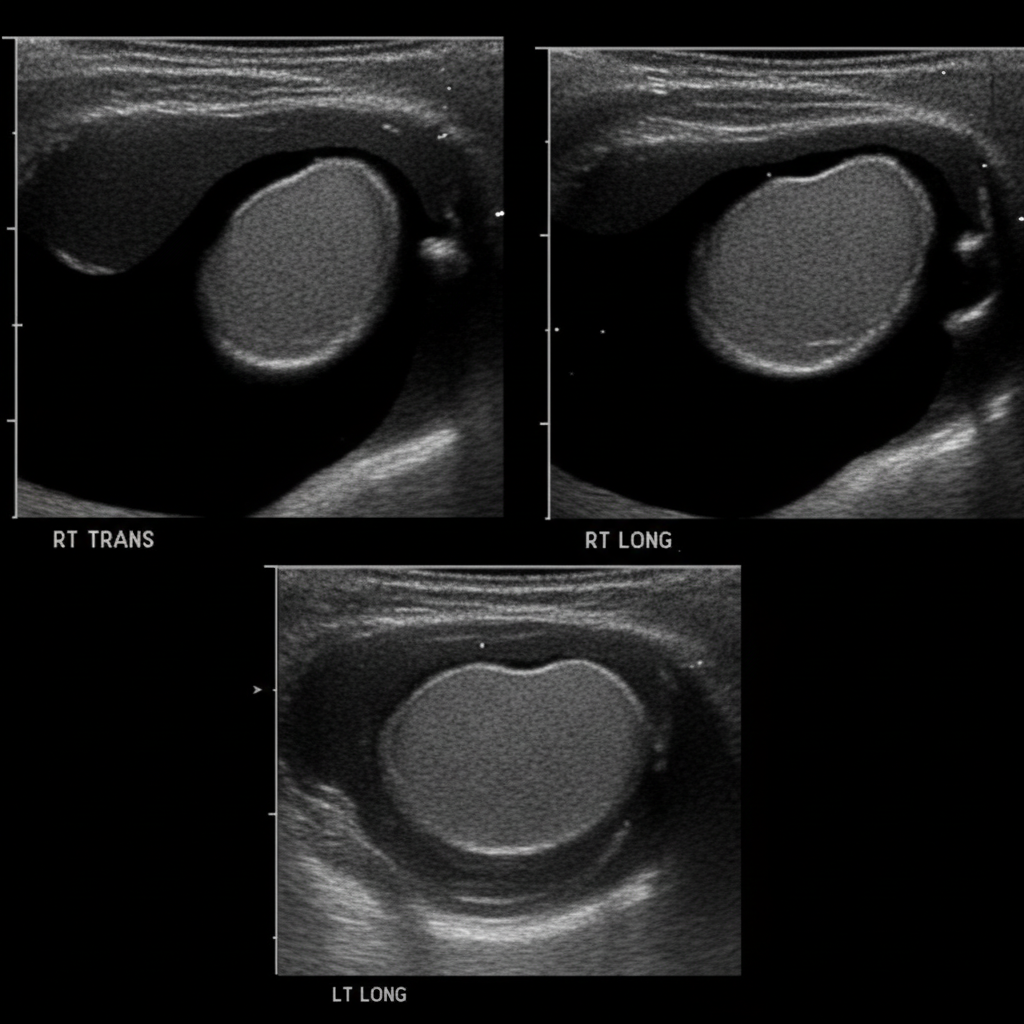

A 5-year-old boy is taken to his pediatrician by his mother for evaluation of painless testicular swelling. His mother says that it became apparent at 1 year of age and has been progressively increasing in size. There is no history of infectious diseases other than the seasonal flu. The boy has no history of trauma or surgery. He has not visited any tropical countries and his vaccinations are up to date. The vital signs are normal for the patient’s age. The physical examination reveals non-tender, fluctuating testicular swelling bilaterally with positive translucency. The swelling decreases slightly in the supine position and there is a positive cough impulse sign. A sonographic image is shown below. Which of the following statements about the patient’s condition is correct?